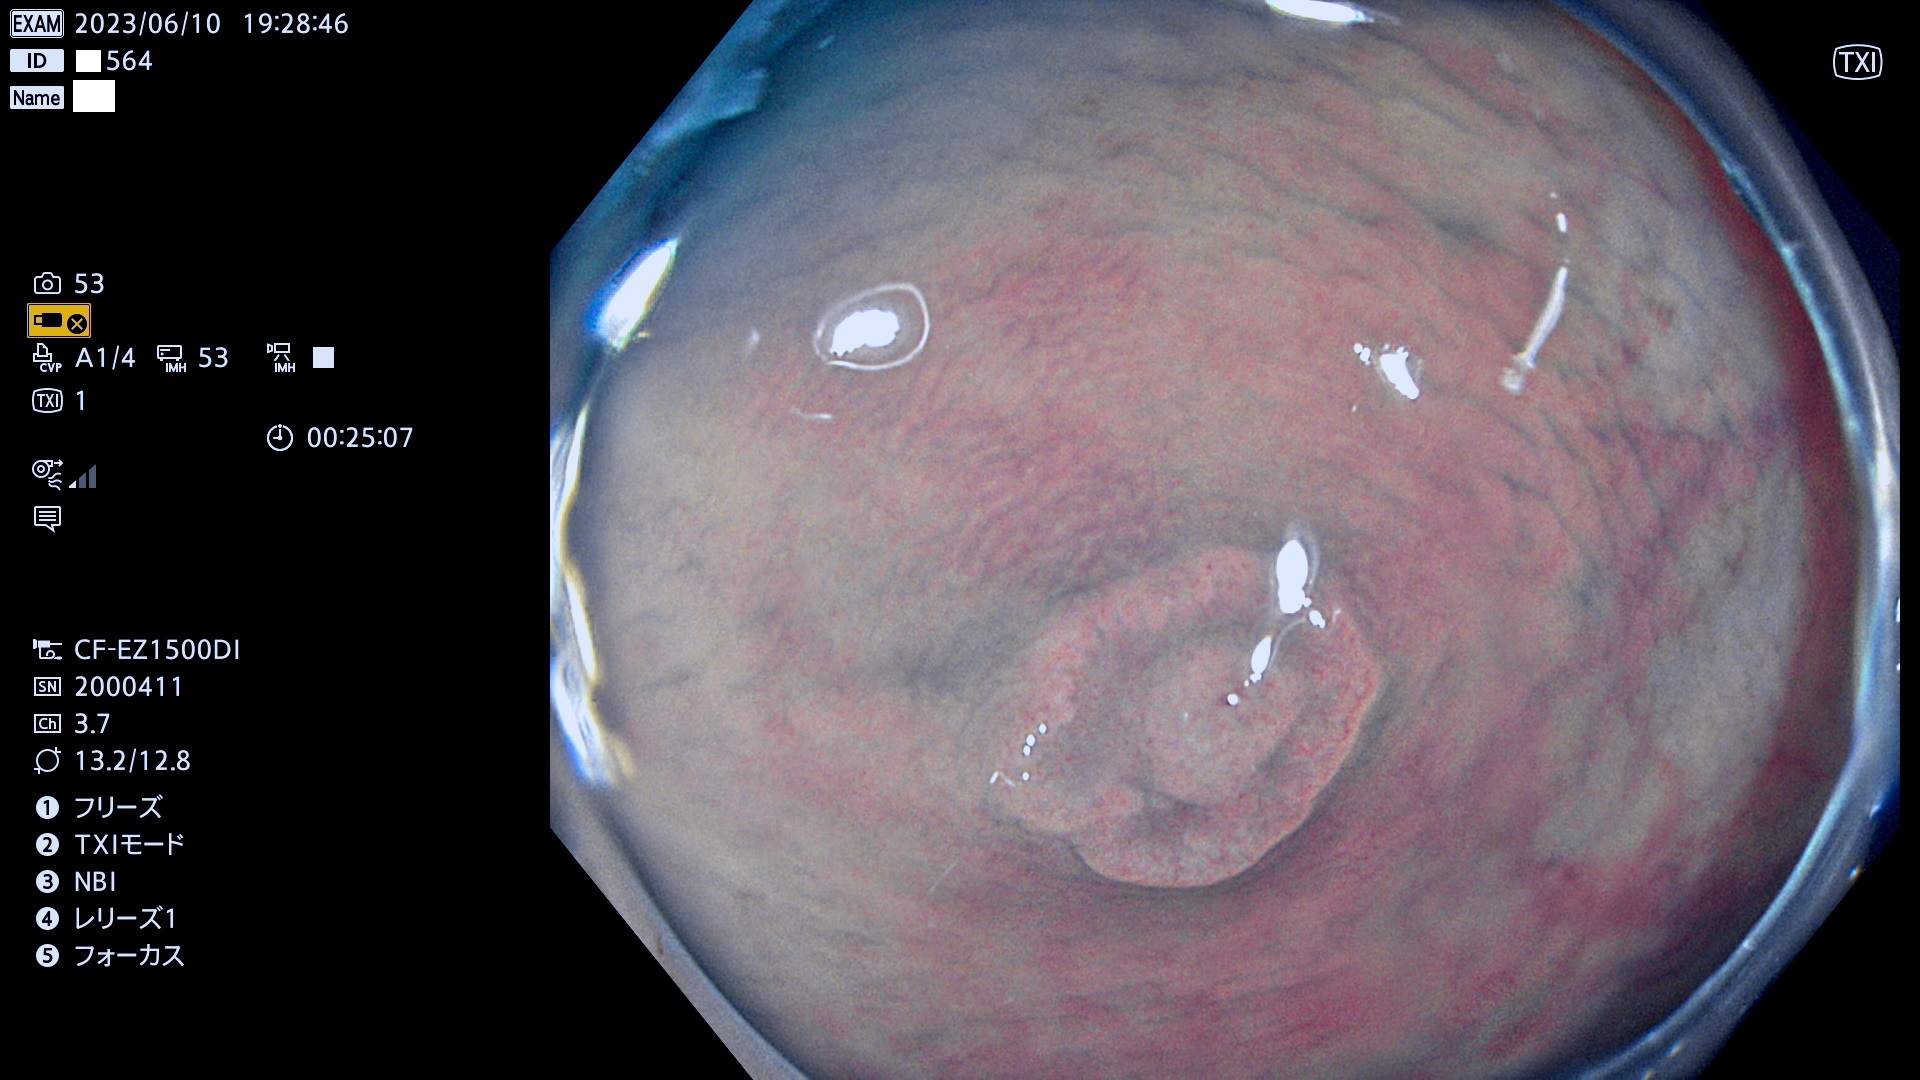

「表面型腫瘍」の中で、完全に平坦な物をUb、陥凹している物をUcと呼びます。平坦隆起型(Ua)よりも、発見が難しく危険な病変です。このタイプの発見率は「腺腫発見率」よりも、遥かに重要な意義があります。

毎週の検査(木・金・土・日)に当院の検査で発見されたUb、Uc病変を、その週の日曜の夜にUPし1週間、提示します。

抽出の対象期間 2023年6月8日(木)〜11(日)の4日間(48件の検査)